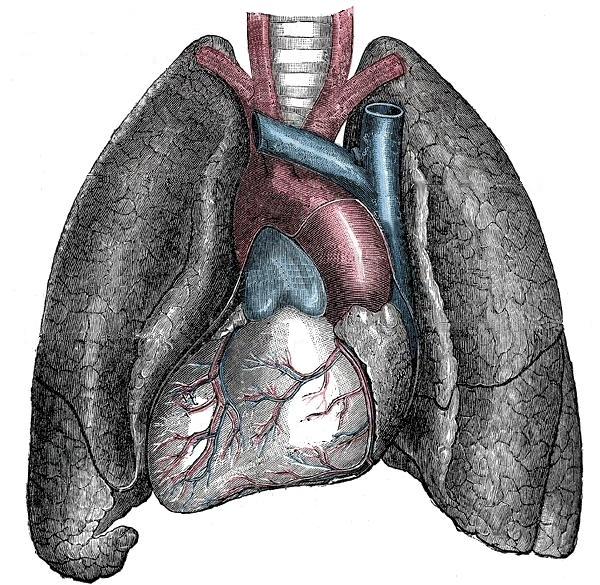

- Естественно, что асимметрия полушарий мозга напрямую связана с генами, определяющими отсутствие симметрии расположения внутренних органов, когда сердце смещено налево, а печень расположена справа. Есть люди, у которых такое расположение нарушено, у них сердце находится справа. Подобное генетическое состояние получило название «ситус инверсус» (Situs inversus [viscerum]), или инвертированное (обращенное, зеркальное) расположение [внутренних органов]. Довольно часто такие люди страдают от нарушений деятельности дыхательной системы, проблем с кожей и слизистыми, расстройств в работе внутренних органов.

Естественно, что подобное нарушение расположения внутренних органов является врождённой патологией, которая некоторых людей не беспокоит. Эта патология часто выявляется лишь случайно, например, в ходе диспансеризации.

Situs viscerum inversus — зеркальное расположение внутренних органов